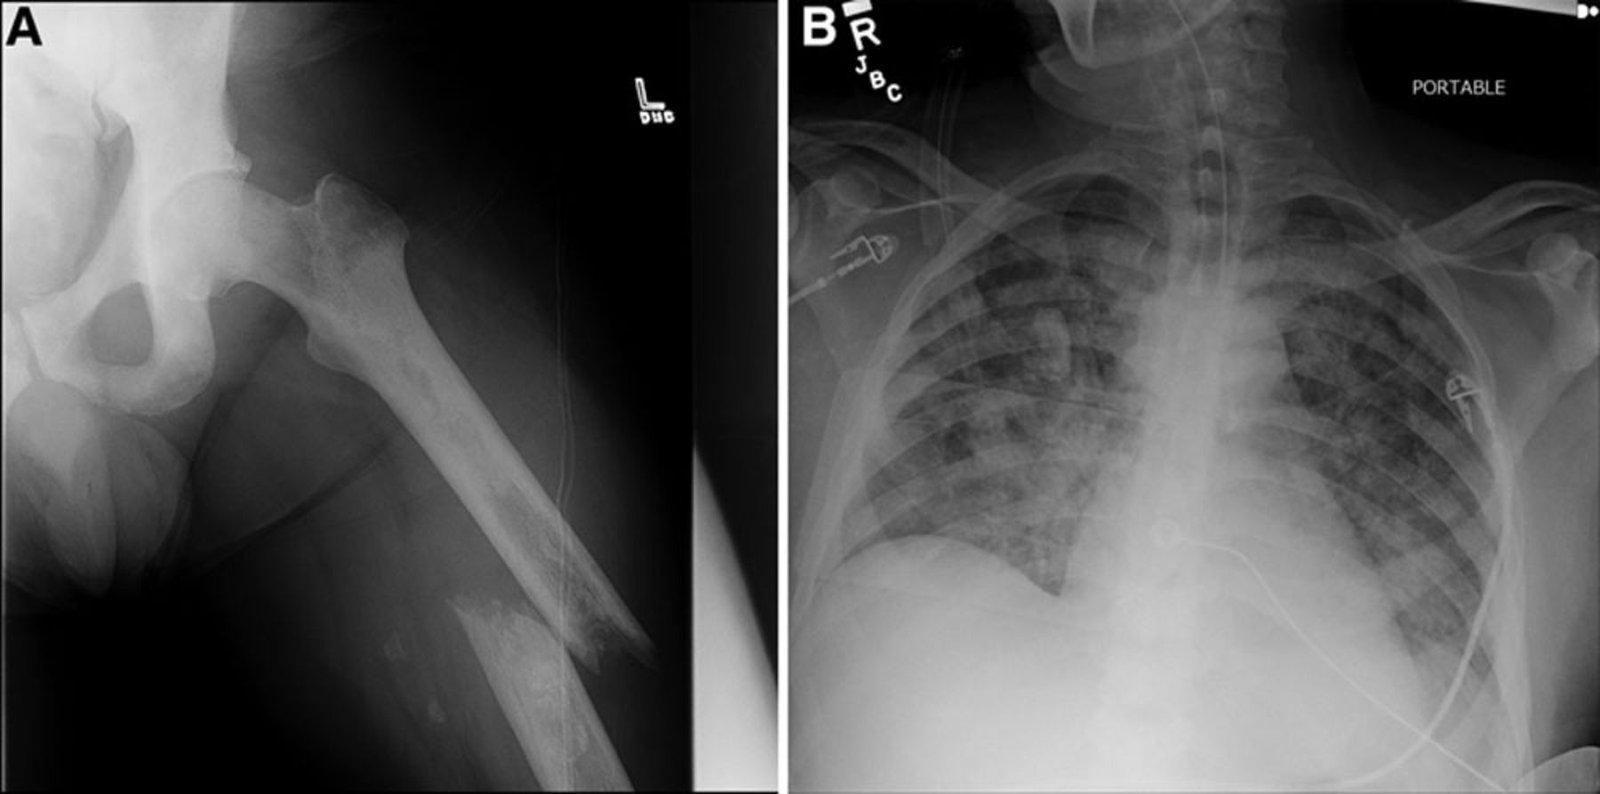

2. Pelvic fracture.

1. X-ray of the chest:

a)lt may snow storm appearance( pathognomic)

b) Increased pulmonary marking.

c) Dialatation of Rt side of heart.